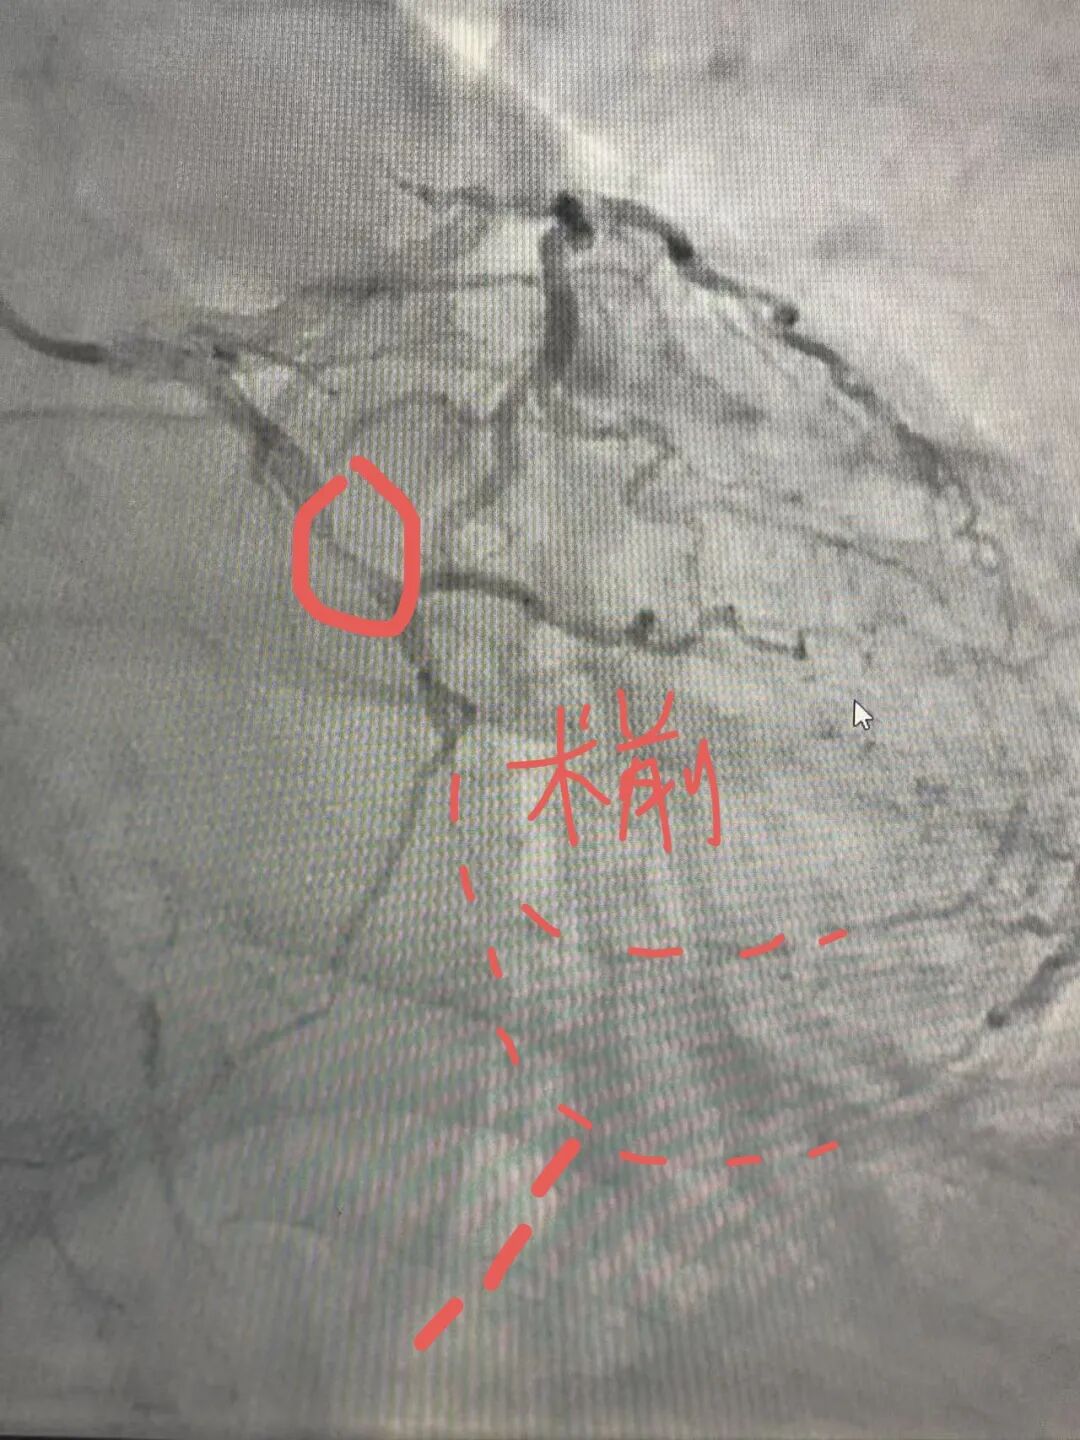

结果显示,患者回旋支严重狭窄,远段完全闭塞,心肌供血严重不足。团队随即决定在病变处施行药物球囊扩张联合药物洗脱支架植入术。经过精细操作,血管狭窄解除,血流恢复通畅。术后患者胸痛症状明显缓解,恢复良好。